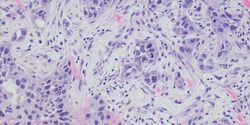

Immunohistochemistry (IHC) has long been used in research and diagnostic laboratories to measure protein expression and localization within tissues. It is an important tool for characterizing heterogenous cell types, such as those found in tumors or brain sections. However, traditional IHC cannot reliably detect more than three protein targets at once.

Multiplexed immunohistochemistry (mIHC) can be used to detect anywhere from three to more than 30 protein targets within a tissue section1. Thus, the technique allows information on a large number of proteins to be collected from a small tissue sample. technology

mIHC is an effective way to extract maximum data from tissues with limited availability. This makes it an ideal tool for studying cellular heterogeneity in oncology and neurology.

Oncology

Failure of cancer treatments is widely attributed to tumor heterogeneity. mIHC on biopsied tissues can aid the rapid classification of tumor subtypes, without using up too much sample. For instance, breast cancer is classified based on the presence or absence of estrogen, progesterone, and Her2 receptors. In one study on breast cancer samples, 32-plex mIHC combined with mass cytometry showed inter-patient variability as well as differences in protein expression within the same tumor2. Such classification can facilitate tailored therapy and disease prognosis.

Immune cells in the tumor microenvironment also affect response to immunotherapy. Using mIHC, researchers labeled head and neck cancer biopsy samples with 12 antibody panels to measure lymphoid and myeloid phenotype in leukocytes3. Myeloid-enriched tumors in the study were associated with lower survival and had poor therapeutic response to the GVAX cancer vaccine. Therefore, mIHC may be used to gain insights into the tumor microenvironment and quantify predictive biomarkers to stratify patients based on their therapeutic response.